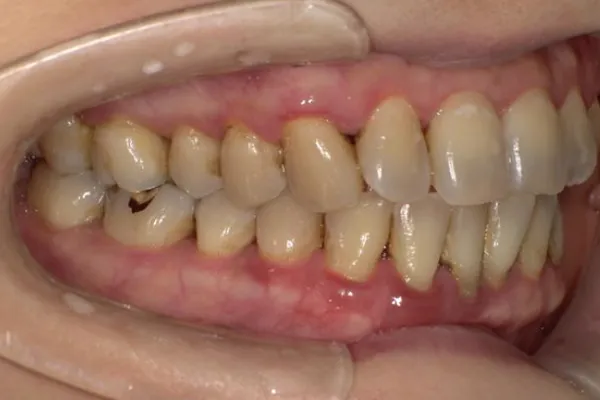

歯周組織再生療法

歯周病で失われた骨や歯ぐきを“再び回復させる”ための治療です。歯を支える力を取り戻し、将来的な抜歯のリスクを減らすことにつながります。

歯を残す最新治療

歯周病により破壊された、歯茎や骨を人工骨や成長因子などを用いて再生させる治療方法です。

将来的に抜歯となるリスクの高い歯などを歯周組織を再生させ、歯を長持ちさせることを目的とします。歯周病でダメになった歯をどうしても残したい方、歯ぐきや歯槽骨を元に戻して歯の寿命をしっかり伸ばしたい方に適応される治療方法です。 -